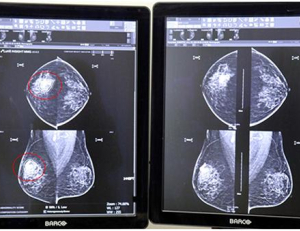

- 건협, 유방암 루닛 인공지능(AI) 판독시스템 도입

한국건강관리협회(이하 건협)는 유방촬영에서의 판독오류를 줄이고 정확도를 높이기 위해 지난 3월 19...